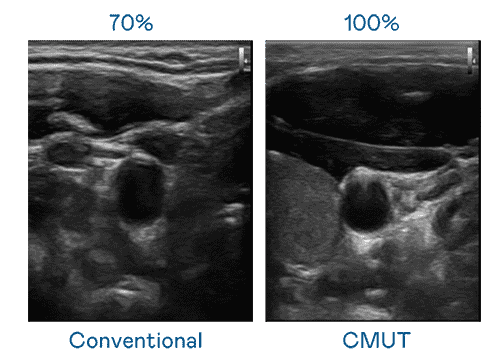

CMUT 技术是一种用电容式微机电元件来产生超音波讯号的技术。。。与传统 PZT 压电式技术相比,,,,CMUT 频宽增加 30%,,,更宽频的超音波讯号让影像解析度大幅提升,,是实现高影像品质医疗超音波扫描、、、、促进精准医疗发展的关键技术。。。

超音波影像的解析度高低,,,,首先取决于探头能发出的讯号频宽。。牛牛游戏 CMUT 可提供高清晰的超音波讯号,,,提供高频宽、、、高灵敏度、、影像纹理细节更高的超音波影像,,,协助医护人员缩短影像判读时间及利用精准的医疗影像进行诊断。。。